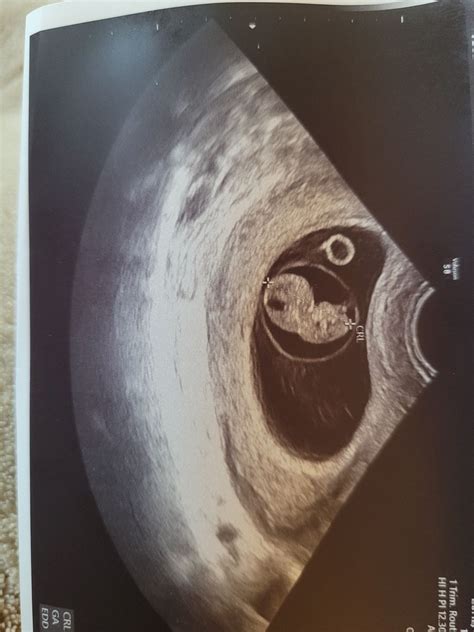

A 9 week ultrasound is a medical imaging procedure that uses high-frequency sound waves to create images of the fetus and the uterus. This non-invasive test is typically performed transabdominally or transvaginally, depending on the preference of the healthcare provider and the position of the uterus. The primary goal of a 9 week ultrasound is to confirm the viability of the pregnancy, assess the fetal heart rate, and measure the size of the fetus.

• Measurement: The healthcare provider will measure the size of the fetus, typically focusing on the crown-rump length (CRL), which is the distance from the top of the head to the bottom of the buttocks. This measurement helps determine the gestational age and overall growth of the fetus.

• Fetal Size: The crown-rump length (CRL) is a critical measurement that helps determine the gestational age. At 9 weeks, the CRL is typically around 21-27 mm.

• Gestational Sac: The gestational sac, which contains the fetus and amniotic fluid, should be visible and measure appropriately for the gestational age.

• Yolk Sac: The yolk sac, which provides early nutrition to the embryo, should also be visible and measure within the expected range.

• Fetal Pole: The fetal pole, which is the earliest visible part of the embryo, should be clearly visible.

• Amniotic Sac: The amniotic sac, which contains the amniotic fluid surrounding the fetus, should be visible and measure appropriately.

• Yolk Sac: The yolk sac, which provides early nutrition to the embryo, should be visible and measure within the expected range.